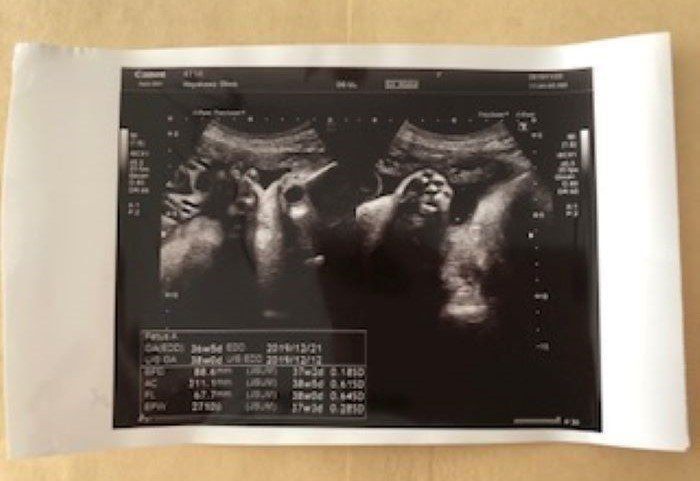

第24週 エコー写真に目線がピッタリ

妊娠24週目の健診時、赤ちゃんがバッチリとこちらに向いている時のエコー写真です。エコー検査で見た赤ちゃんは、顔を左右に動かしたり、手足をバタバタと器用に動かしたりと、子宮内の環境にすっかり馴染んでいるように私には見えました。左の写真はパンチをした瞬間です。エコー検査の間も何回か胎動を感じていました。